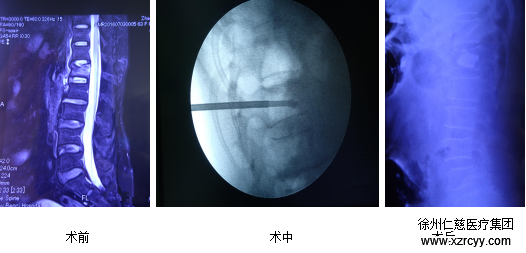

张冶医生在给郝奶奶手术中

在了解了郝奶奶的伤情后,sararz骨科团队建议手术治疗,并为其制定了私人的治疗方案。 在伤后第三天sararz骨科医生为郝奶奶做了微创脊柱椎体成形术,术后患者疼痛消失,第二天即下床活动,治疗效果良好。